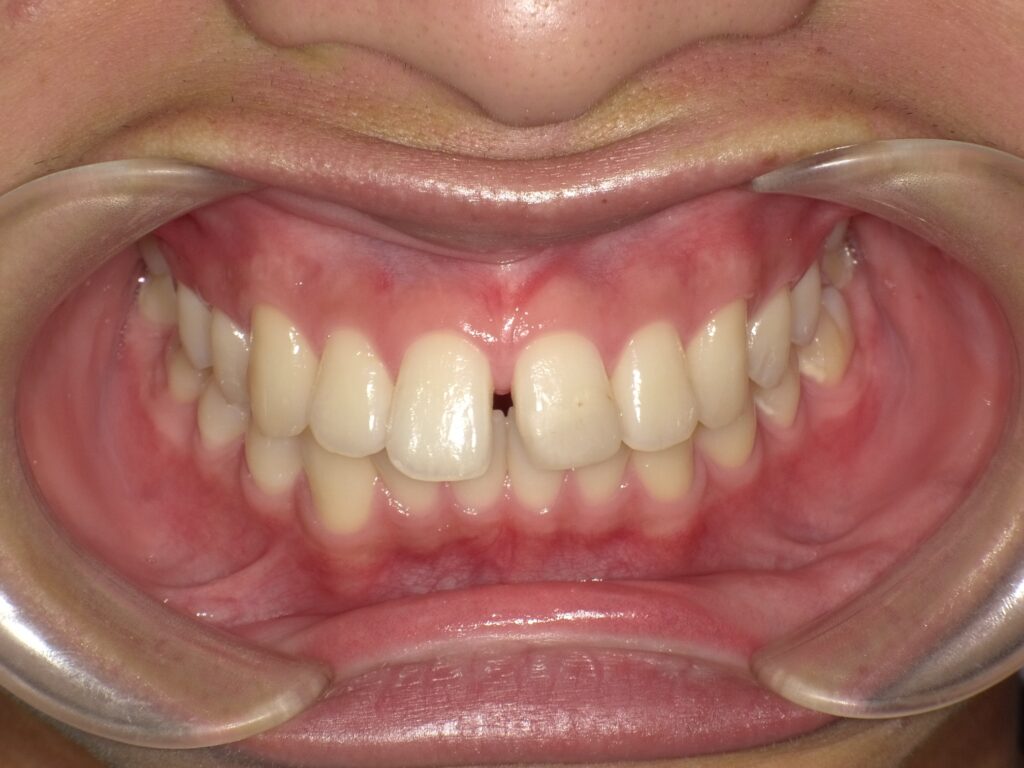

治療前